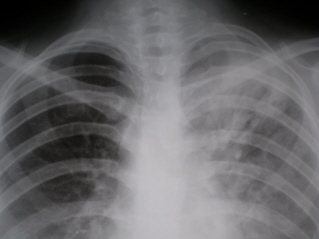

Инфильтративный туберкулез (обзорный снимок + томограмма). В верхней доле левого легкого определяется участок инфильтрации неправильной формы, размером 6 х 7 см. Интенсивность участка средняя, без четких контуров